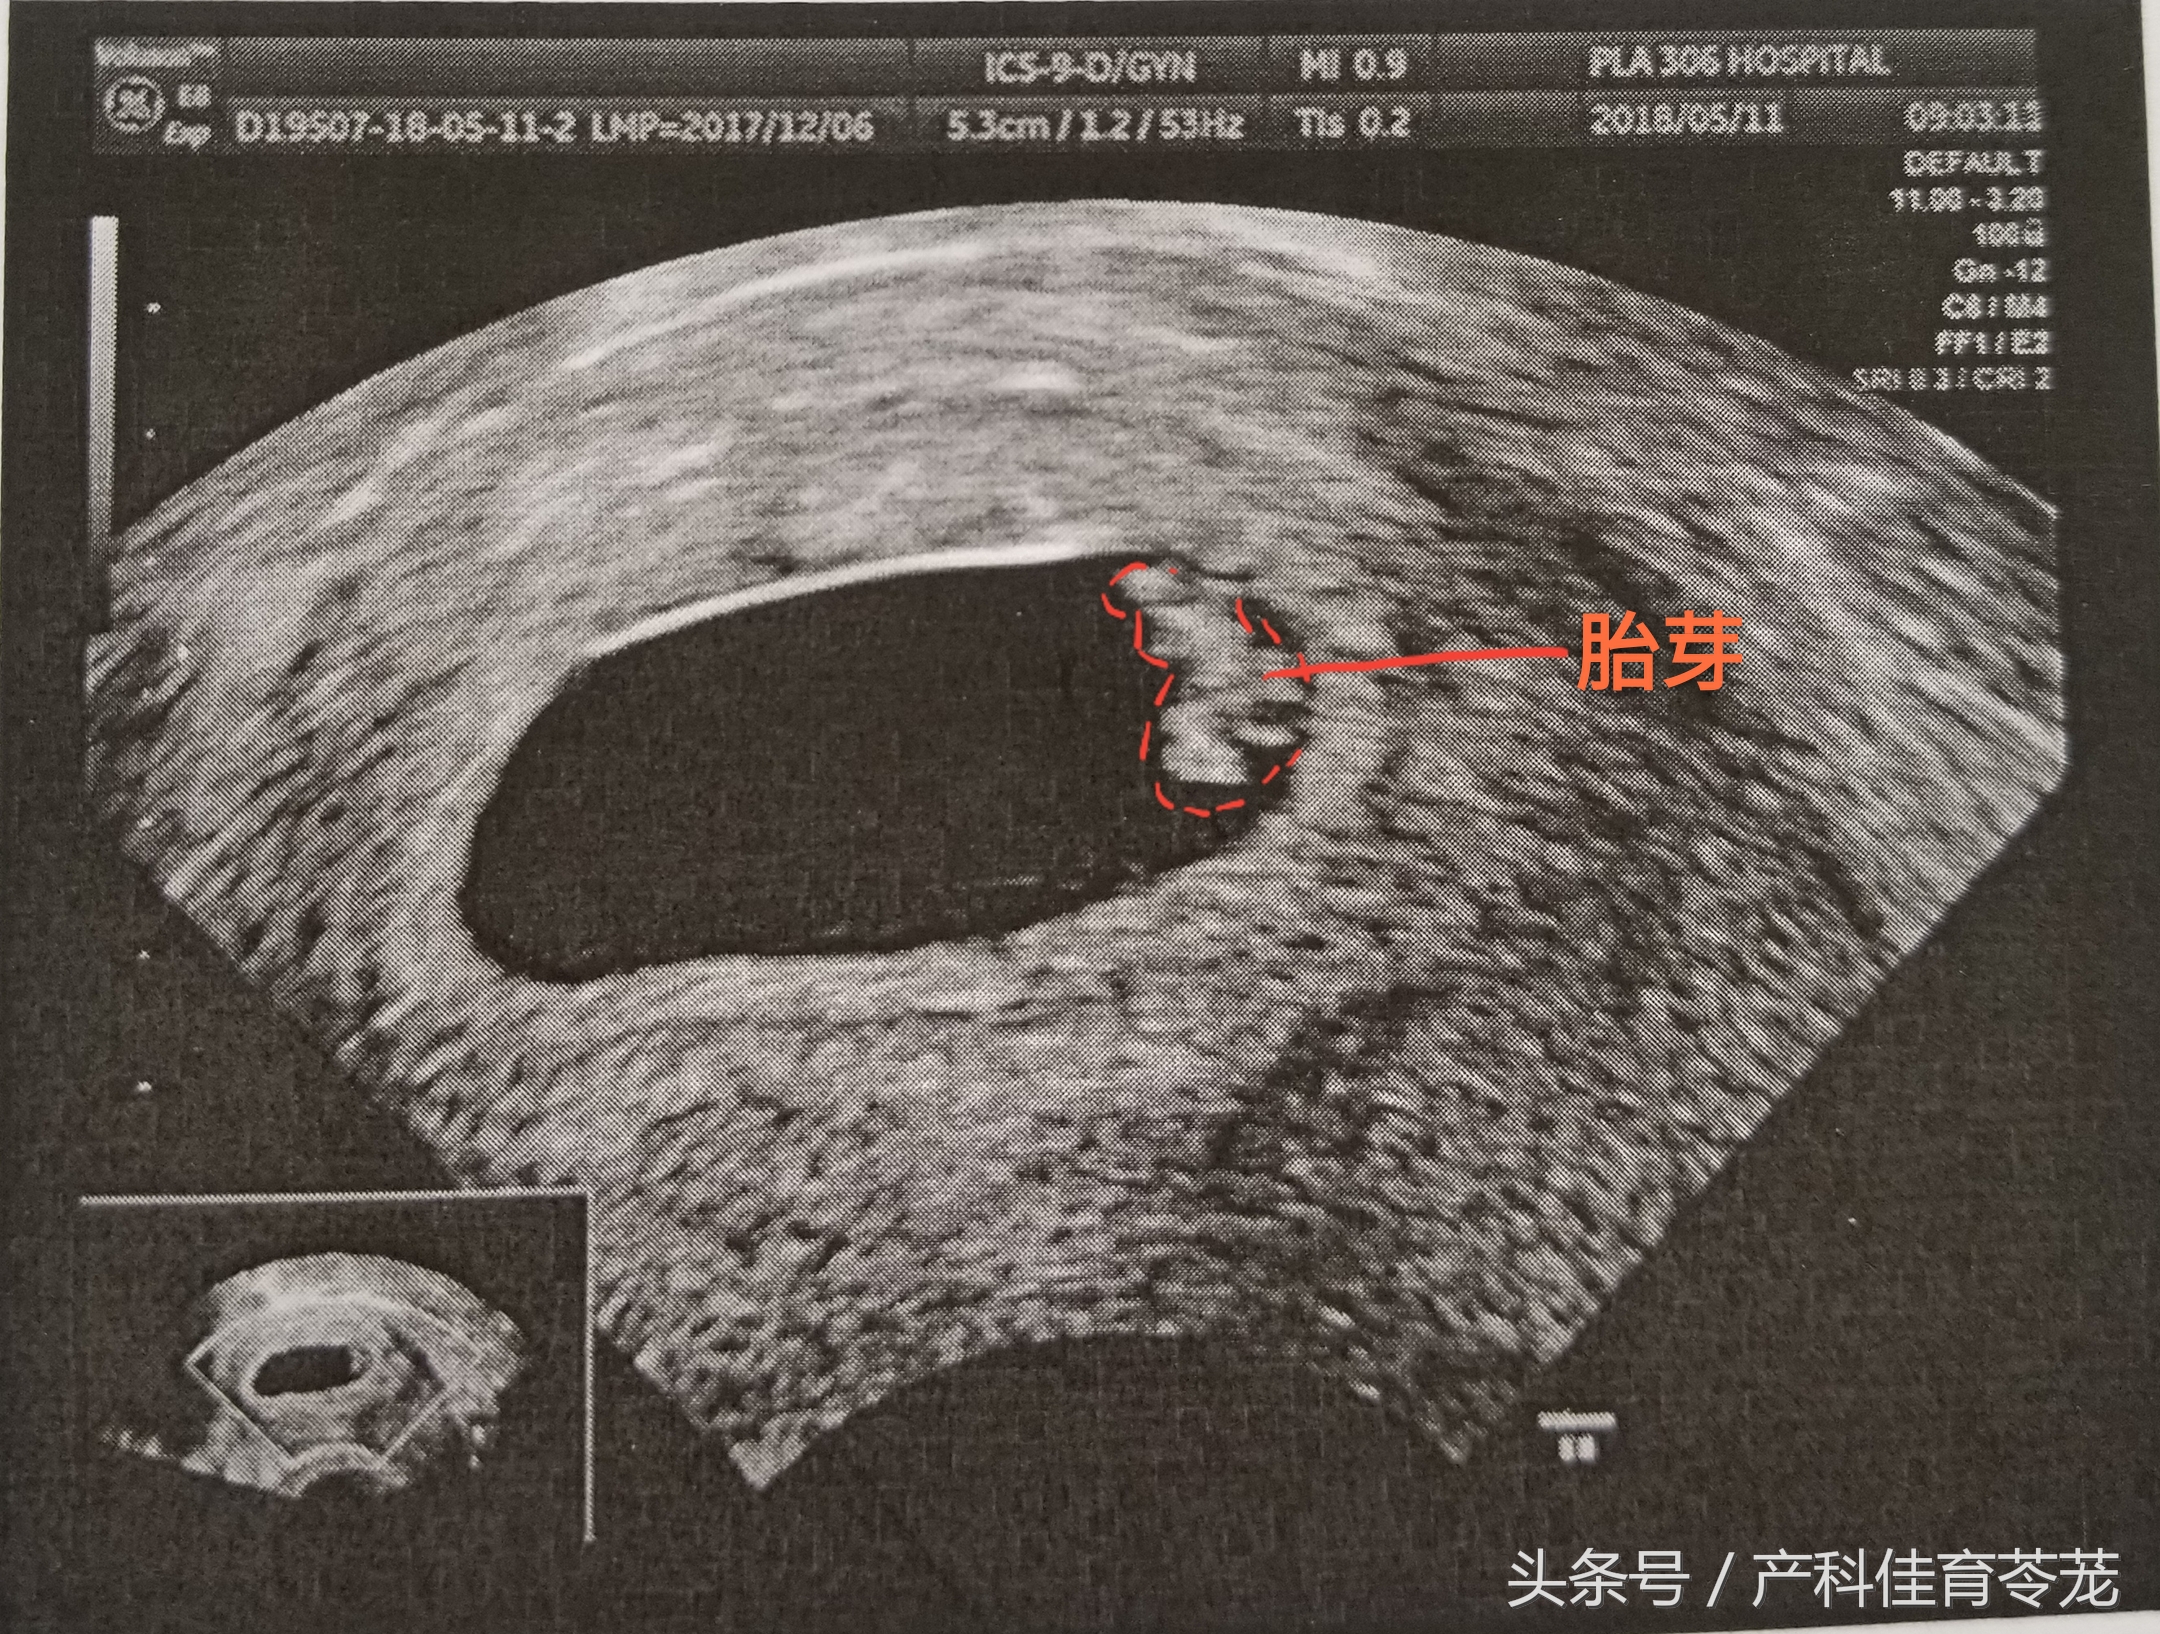

三、胎芽(Fetal Pole)

只有出现胎芽,才能明确是宫内妊娠。

胎芽的增长速度为1mm/d,到妊娠53天时可以长到12mm。

胎芽长度达2mm或以上就可以看到胎心搏动,但也有5-10%的2-4mm的胚胎仍然看不到明显的胎心搏动。